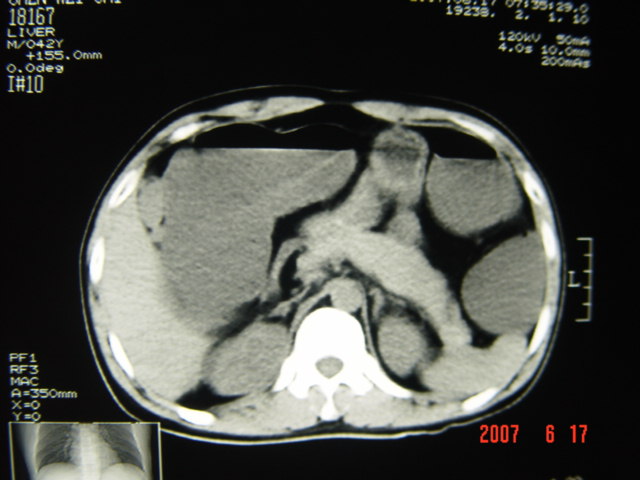

[br][br]以下是引用lkc8963在2007-6-17 13:32:00的发言:[br]完全支持邓主任意见:降/乙交界部占位性病变伴不全梗阻.做个增强或者be可能更好.